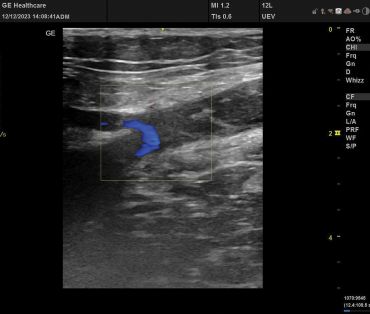

Obr. 4 Nález po endovenózním zákrokuNámi provedený endovenózní zákrok byl spojen s očekávaným efektem, obě insuficientní kmenové žíly (VSM l. dx a VSM l. sin) byly uzavřeny od safenofemorální junkce (obr. 4). Nález z našeho pohledu byl uspokojivý i z hlediska EHIT (Endothermal heat‑induced thrombosis), který byl dle Kabnickovy klasifikace ve stadiu 0. Byly též uzavřeny epifasciální varikozity po provedené pěnové sklerotizaci.